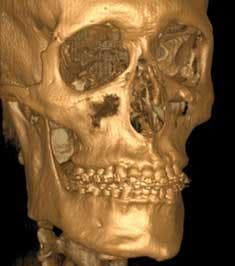

Specialized 3–D reconstructive software also allows practitioners to provide 3–D images and viewer software to the referring dentist, allowing for collaboration regarding positioning, placement, and angulation of implants prior to surgical placement procedures (Fig. 3).

Orthodontists and oral surgeons often need the extended field of view for cephalometric radiographs and orthognathic treatment planning, and viewing cranial facial deformities, pathology, and trauma (Fig. 5). It is important to note that with a fully extended field of view scan, the dentist is responsible for interpreting or having someone else interpret the scan to detect pathology within the confines of the scan. It is not sufficient from a liability standpoint to address the dental issues alone.